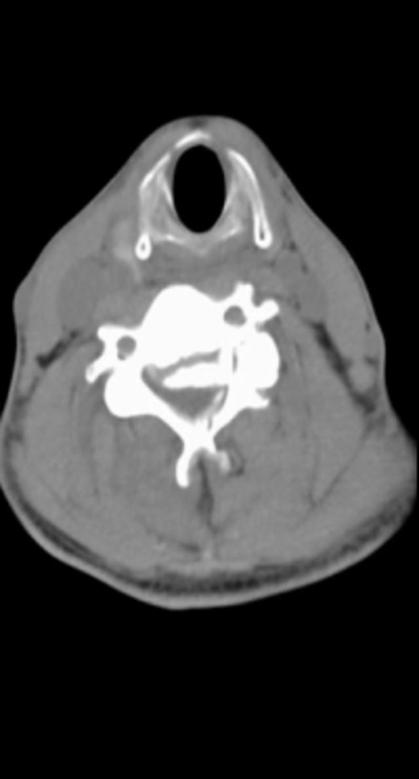

工友们赶紧把沈先生送到了南方医科大学深圳医院,急诊科迅速响应,临时制动颈椎,安排相关检查,并通知骨科紧急会诊。骨科主任桑宏勋教授带着医生们迅速赶到,“从检查结果来看,患者伤情非常严重,颈椎骨折脱位,脊髓高位损伤。由于脊髓损伤位置较高,水肿平面还在上升,连胸廓肌肉功能也丧失,肋间肌、膈肌瘫痪,严重影响到患者的呼吸。通俗地说,就是高位截瘫。”检查后,桑宏勋主任立刻安排患者入院并进行紧急处理,他提出早期激素冲击保护脊髓的治疗方案,同时尽快先为患者进行颅骨牵引术,重建颈椎的稳定结构,减缓损伤继续进展。